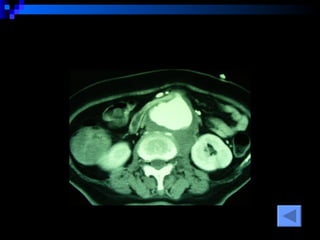

CT SCAN AAA juxtrareal -> bifurcation  Size 10*8*4 cm Inflamatory tissue  around AAA Intact renal artery Aortic dissection at juxtra renal -> bifurcation Bowel wall thickening at 3 rd -4 th  part of duodenum

CT SCAN AAAjuxtrareal -> bifurcation Size 10*8*4 cm Inflamatory tissue around AAA Intact renal artery Aortic dissection at juxtra renal -> bifurcation Bowel wall thickening at 3 rd -4 th part of duodenum